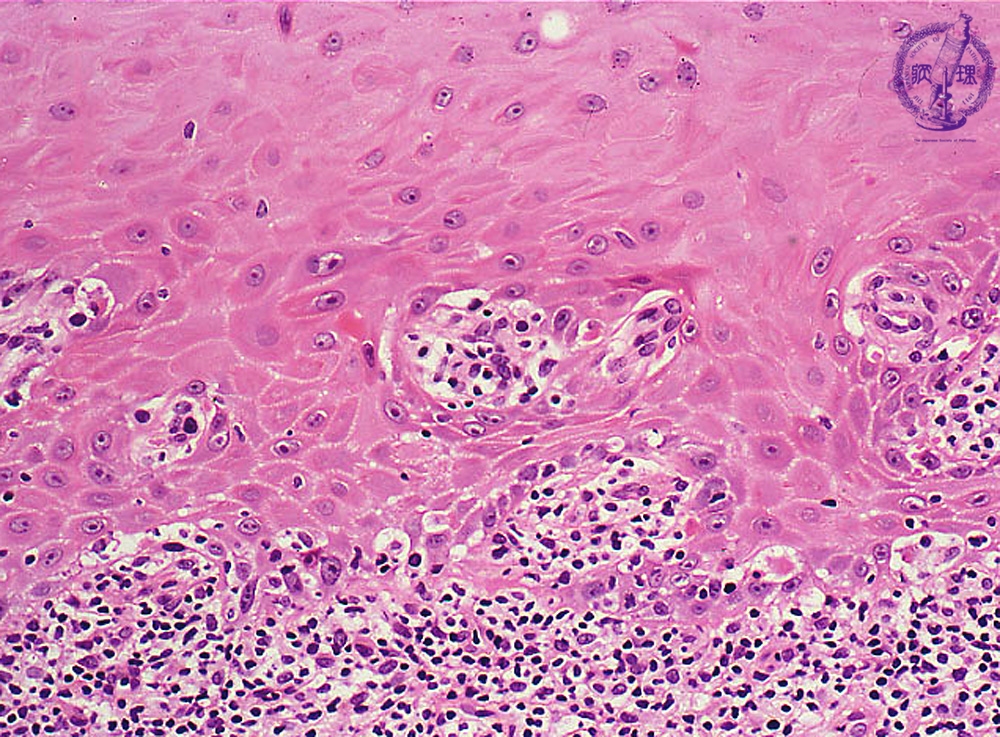

Microscopic finding (HE stain, high-power view):The basal cells show vacuolar change, or hydropic (liquefaction) degeneration (black arrows) and there is cleft formation between the epidermis and papillary dermis. Colloid bodies (degenerating keratinocytes) (red arrow) are seen in the epithelium.